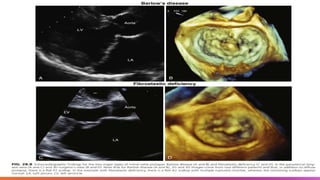

Clinically important MV prolapse/flail

typically presents as two types :

Barlow disease: is an infiltrative disease characterized by

excessive myxomatous tissue associated with

mucopolysaccharide accumulation that can affect one or both

leaflets, and chordae.

In Barlow disease, there is thickening of the leaflets leading to

redundant valvular tissue and frequently elongated or ruptured

chordae.

Patients with Barlow disease are usually diagnosed in young

adulthood and typically present with bileaflet and

multisegmental prolapse with or without flail scallops

Fibroelastic deficiency, which is the most common form of degenerative

MR in the MV prolapse spectrum, the loss of mechanical valve integrity due

to abnormal connective tissue structure and function is the most common

finding.

Patients with fibroelastic deficiency are usually identified in their 60s.

Typically present with localized and unisegmental prolapse or flail

Barlow’s Disease vs

Fiobroelastic

Deficiency

• Clear distinction between these

two entities is difficult because it

has been suggested that they

constitute the different ends of a

disease spectrum with some

valves not demonstrating the

typical appearance of Barlow

disease but having myxoid

infiltration on histopathological

exam.